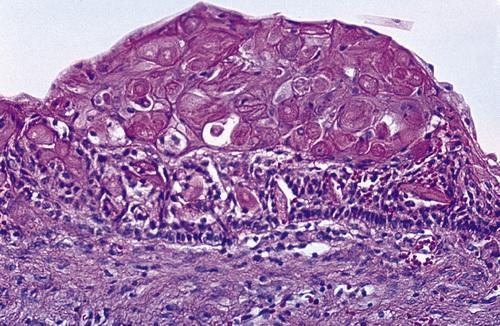

High-power view of a dentigerous cyst from a 53-year-old man. The lining demonstrates full-thickness epithelial dysplasia.

odontogenic carcinoma

A dentigerous cyst from a 53-year-old man showing islands of invasive epithelial cells in the cyst wall.